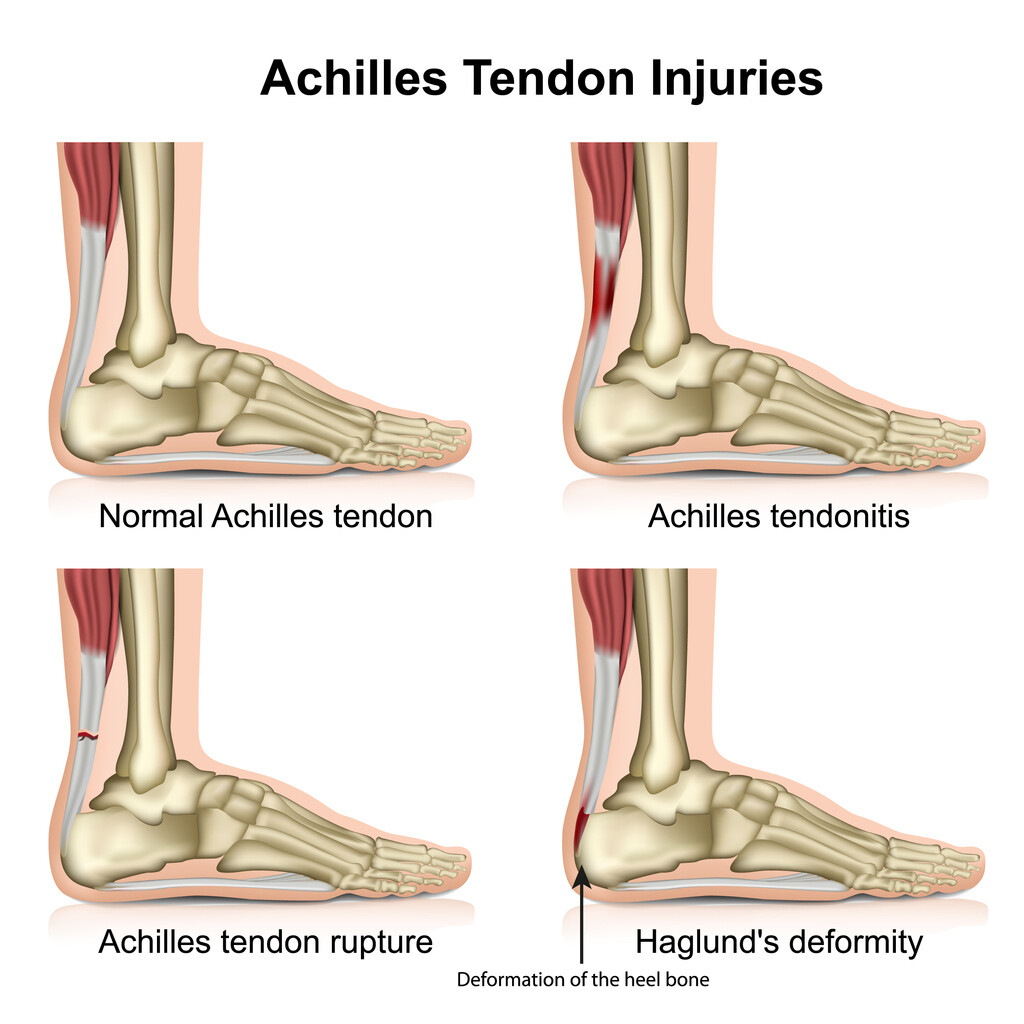

Achilles tendon injuries often cause pain, stiffness, and swelling in the back of your leg near your heel.

Achilles tendon injury prevention. For people with more severe injuries, a doctor may recommend surgery. Treatment treatment for a ruptured achilles tendon often depends on your age, activity level and the severity of your injury.

Using ice and resting may help, but you also want to keep your tendon from moving around too much. It mainly occurs in people playing recreational sports, but it can happen to anyone. Achilles tendinitis treatment includes rest, physical therapy and supportive shoes.

We show you only the best treatments for your condition and symptoms—all vetted by our medical team. She will make the correct diagnosis and develop an individualized treatment plan for your specific injury. Warmth around the heel or along the tendon difficulty standing on your toes thickening of the achilles tendon causes of achilles tendinitis